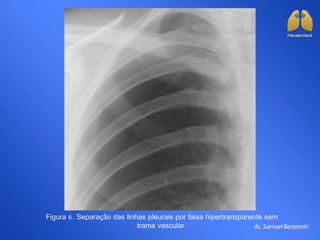

Figura 6. Separação das linhas pleurais por faixa hipertransparente sem

trama vascular.

Figura 6. Separaçãodas linhas pleurais por faixa hipertransparente sem trama vascular.